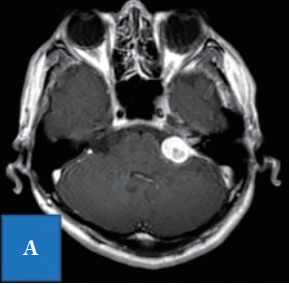

术前MRI结果显示肿瘤已进展至内耳道,根据影像学检查结果诊断为听神经瘤,肿瘤直径为24mm。

入院时T1-加权项磁共振成像显示,延伸到内听道的桥脑角均匀增强